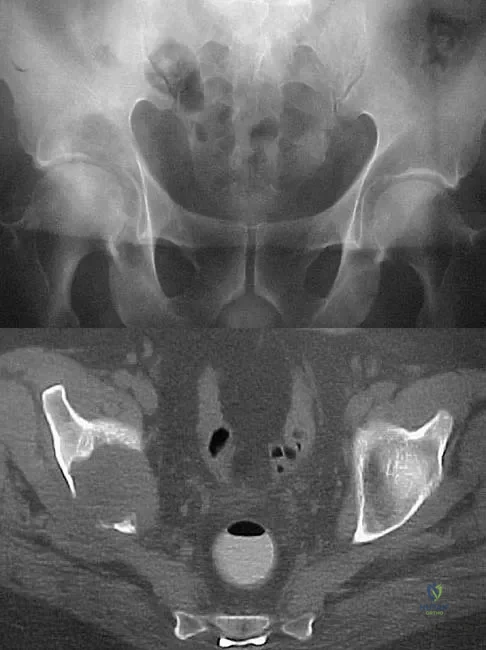

A 25-year-old patient who sustained multiple bilateral rib fractures, a pulmonary contusion, a left nondisplaced transtectal acetabular fracture, and a closed humerus fracture in a motor vehicle accident 2 weeks ago is transferred from another hospital. The humerus fracture has been surgically treated. There are no signs of infection, and the trauma surgeon wants to mobilize the patient as soon as possible. Radiographs are shown in Figures 15a and 15b. Management of the humerus fracture should consist of

Explanation